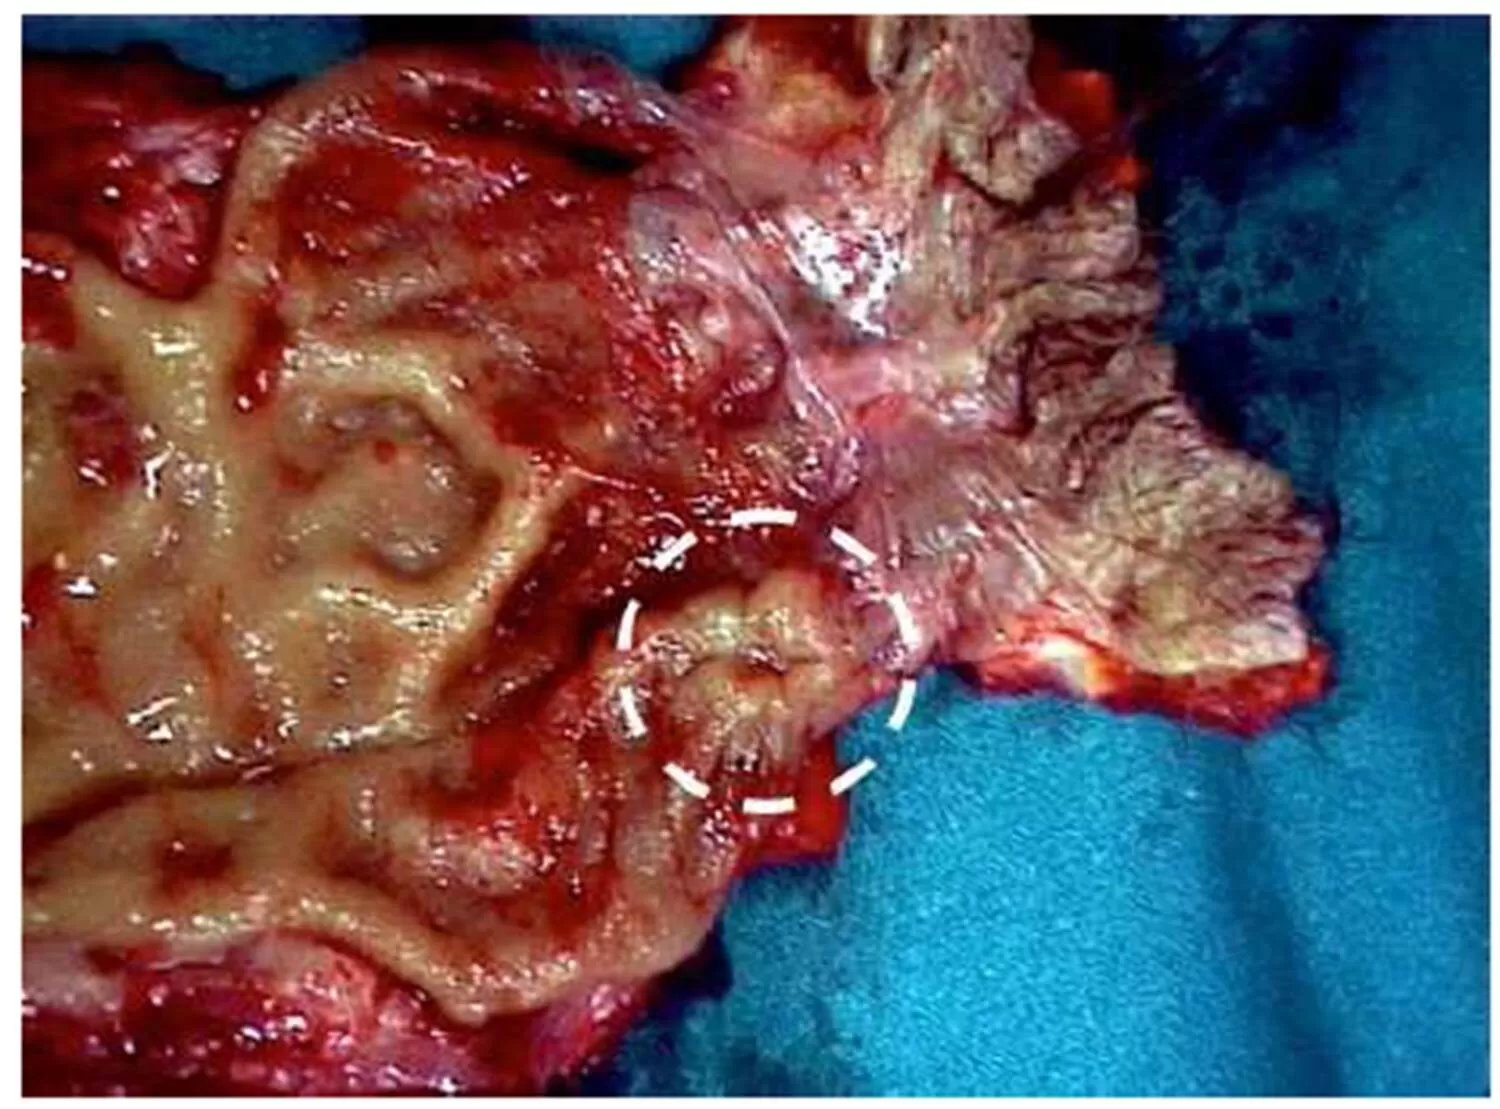

A 78 years old male presented to our department with an endoscopic diagnosis of rectal neoplasia. The only referred symptom was mild anal bleeding. Tumor’s endoscopic appearance was of a flat centimetric polyp of the posterior rectal mucosa, less than 1 cm above the anorectal junction. Blood tumor markers (CA19.9, CEA) were negative. Biopsy resulted suggestive for a poorly differentiated solid neoplasia; immunochemistry was positive for Melan-A, S-100 protein, HMB-45 and Vimentin suggestive for rectal melanoma. Dermatological, Otolaryngology and Oculist counseling excluded other melanoma localization, and the lesion was then considered a rectal PMM. A CT scan showed no sign of parenchimal or lymphatic metastases while revealing an irregular inspissation of the lower rectum. A total body 18F-FDG PET-CT scan confirmed an isolated pathological activity of the posterior rectal wall with no other sign of captation. Eco-endoscopy showed infiltration of the submucosal layer with no mesorectal lymph-adenophaty. The patient underwent abdomino-perineal amputation (Miles’ procedure) with iliac lymphnodes dissection and definitive pathology confirmed the presence of a primitive malignant amelanotic melanoma of the lower rectum (Fig.1) focally infiltrating the submucosa with no lymphatic invasion of the mesorectal and internal iliac stations (T2N0M0). Previous byopsic immunochemistry was confirmed, and replication index was 30% (Ki67-Mib1). Post-operative course was complicated by prolonged ileus resolved with prokinetic drugs administration. The patient did not undergo any adjuvant chemotherapy. Instrumental and clinical follow up including abdominal US and 18F-FDG PET-CT scan was performed every 6 months with no evidence of local or systemic tumor relapse. After 48 months the patient is in good clinical conditions and remains disease free.

Figure 1:  Surgical specimen: primitive malignant amelanotic melanoma of the lower rectum.